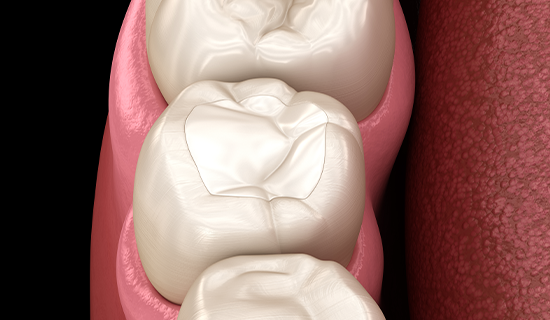

충치가 깊어도 치수를 살릴 수 있는 경우, 저희는 신경치료를 진행하지 않고 최대한 자연치아를 보존하는 것을 목표로 치료합니다. 치아의 신경은 치아의 생명력을 유지하는 중요한 역할을 하기 때문에, 이를 살릴 수 있다면 자연치아를 깎는 범위를 최소화하여 건강한 상태를 유지하는 것이 최선입니다.

충치 부위를 정밀하게 제거하고, 남아 있는 치아 구조를 최대한 보존하며 생체친화적인 재료를 사용해 치료를 진행합니다. 자연치아를 적게 깎는 치료는 치아의 강도를 유지하고, 장기적으로 환자분의 구강 건강에 긍정적인 영향을 미칩니다. 자연치아는 한번 손상되면 복원이 어려운 만큼, 건강한 치아를 최대한 보존할 수 있는 치료를 제공하는 것이 저희의 목표입니다.

충치 치료로도 자연치아를 살릴 수 있는 길이 열려 있습니다.